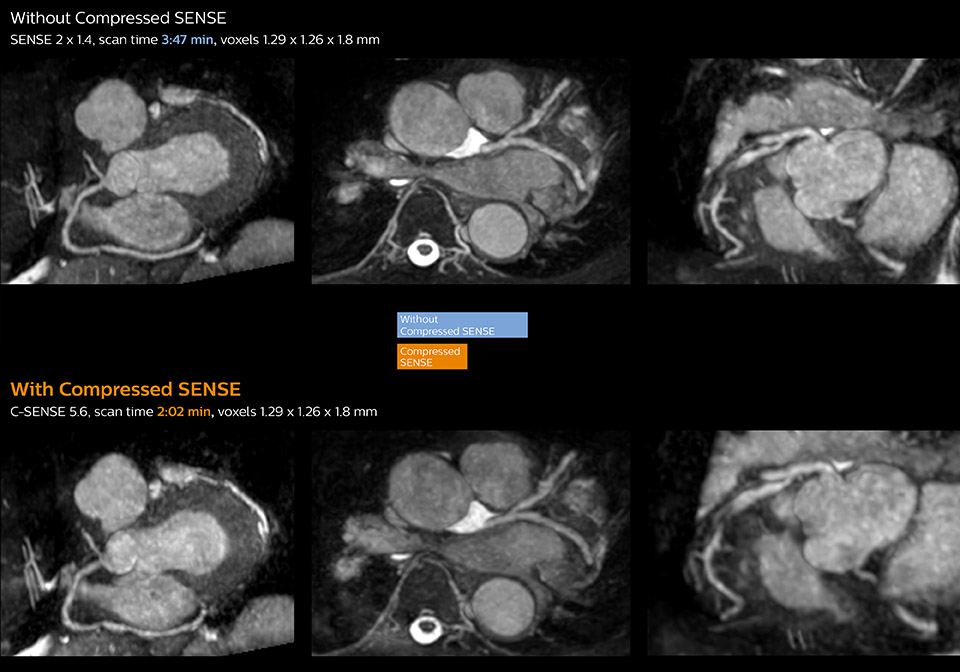

3D whole heart MRI and coronary arteries w/wo Compressed SENSE

These images with and without Compressed SENSE were acquired on Ingenia 1.5T.

View ExamCard: Ingenia 1.5T Cardiac imaging with Compressed SENSE - Kurashiki

clinical image whole heart mri compressed sense desktop